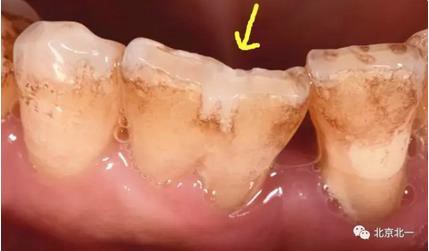

附:關(guān)注箭頭所示,診斷為結(jié)合牙還是融合牙?牙冠結(jié)合一起, 牙根分開。